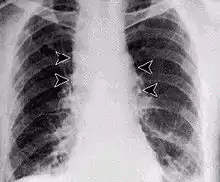

Inhalation anthrax usually develops within a week after exposure, but may take up to 2 months. During the first few days of illness, most people have fever, chills, and fatigue. These symptoms may be accompanied by cough, shortness of breath, chest pain, and nausea or vomiting, making inhalation anthrax difficult to distinguish from influenza and community-acquired pneumonia. This is often described as the prodromal period.[26]

Over the next day or so, shortness of breath, cough, and chest pain become more common, and complaints not involving the chest such as nausea, vomiting, altered mental status, sweats, and headache develop in one-third or more of people. Upper respiratory tract symptoms occur in only a quarter of people, and muscle pains are rare. Altered mental status or shortness of breath generally brings people to healthcare and marks the fulminant phase of illness.

It infects the lymph nodes in the chest first, rather than the lungs themselves, a condition called hemorrhagic mediastinitis, causing bloody fluid to accumulate in the chest cavity, thereby causing shortness of breath. The second (pneumonia) stage occurs when the infection spreads from the lymph nodes to the lungs. Symptoms of the second stage develop suddenly within hours or days after the first stage. Symptoms include high fever, extreme shortness of breath, shock, and rapid death within 48 hours in fatal cases.[27]